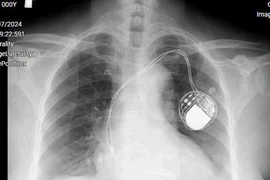

(khoahocdoisong.vn) - Nếu người bệnh đã đặt máy tạo nhịp rồi mà vẫn còn mệt, cần xem nguyên nhân mệt mỏi là vì nhịp chậm hay vì nhịp nhanh. Rung nhĩ có nhiều trường hợp phải đặt máy tạo nhịp, nhưng đặt máy tạo nhịp không có nghĩa là đặt xong thì người bệnh khỏi hết tất cả các triệu chứng.